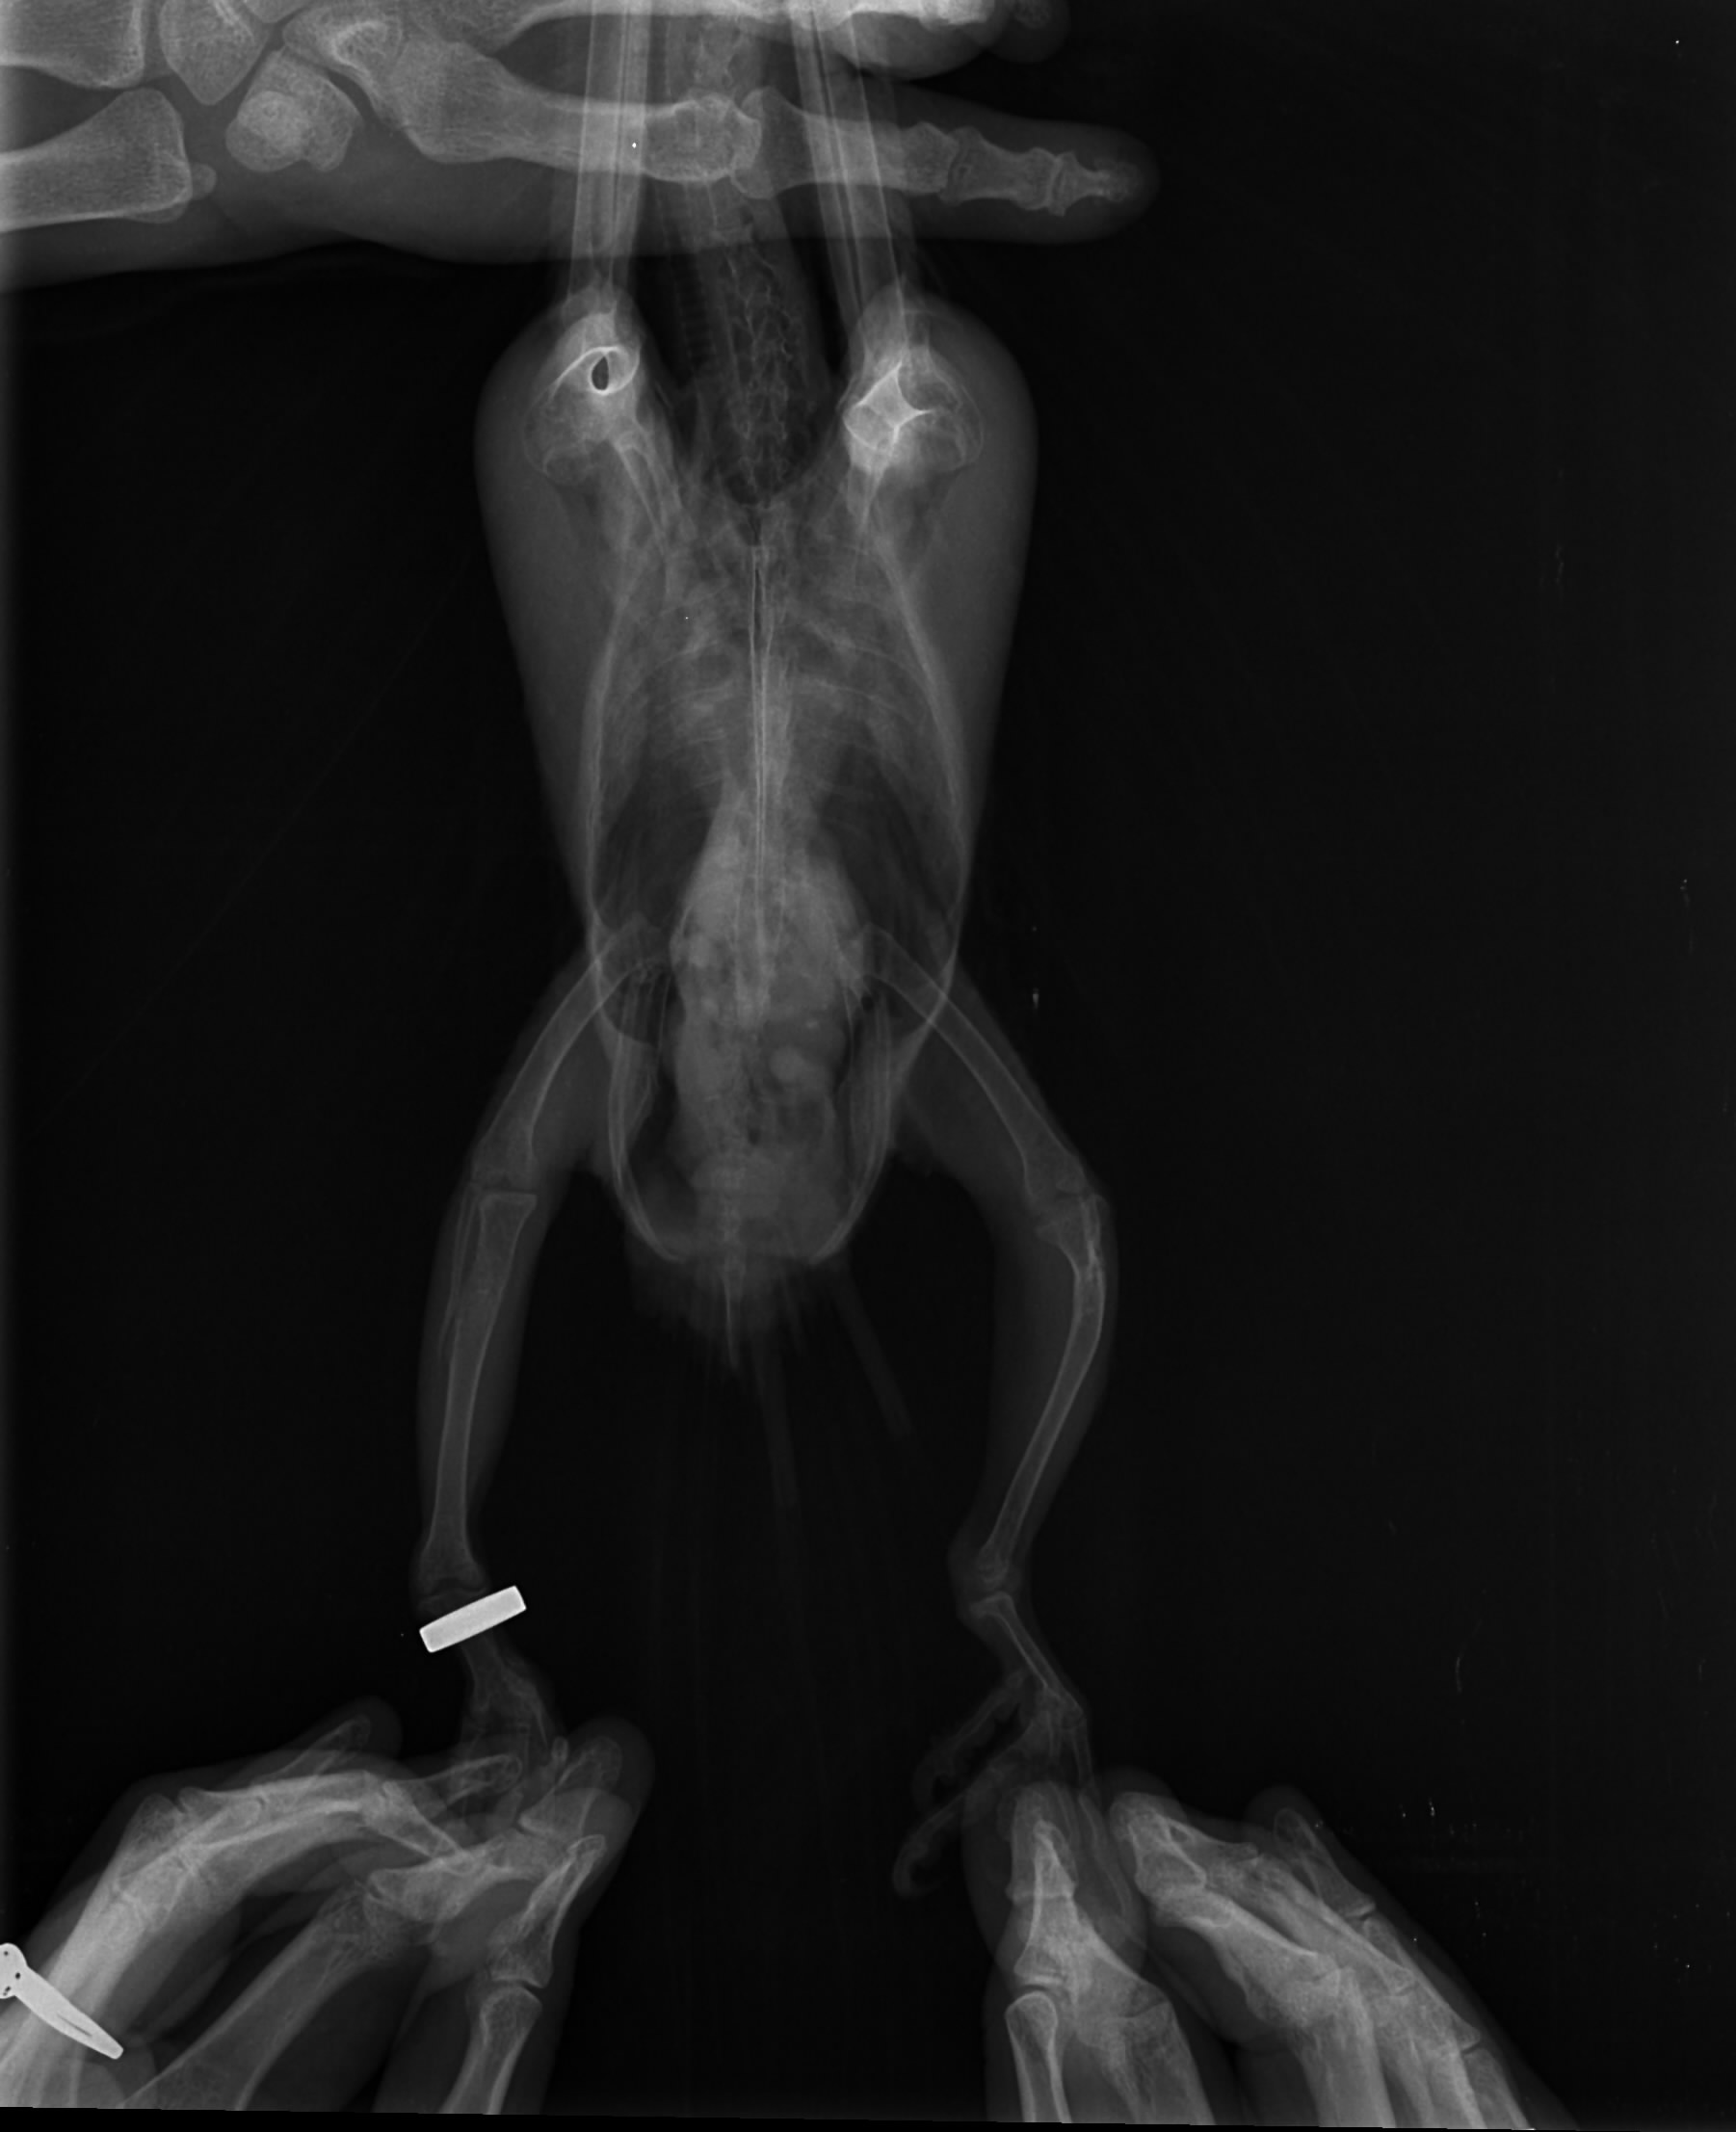

Witam i proszę o pomoc. Może ktoś z Was miał już takie problemy. Mam młodą lorke od hodowcy z forum nie będę teraz rozwodzić się na temat tego od kogo i dlaczego ale młody nie chce latać. Pierwszy raz mam taką sytuację , że młoda półroczna papuga nie chce latać. Od samego początku podkurczał łapki w piąstkę ale składałam to na karb masy ciała bo był dużym pisklakiem. Niestety nie wyłapałam tego wcześniej i za to się obwiniam :( Ma okropnie krzywe kości. Dojechał do mnie jak miał prawie 3 miesiące więc ten intensywny wzrost już był zakończony. Ptak wówczas już nie przyrasta na masie a wręcz ją gubi na usamodzielnieniu. Dokarmiałam go jeszcze miesiąc dokładając wapń do papki dwa razy w tygodniu ze względu na silne przebarwienia na skrzydłach (zółte lusterka) Ale nie wyłapałam tak silnej krzywicy w układzie kostnym. Na zdjęciu rtg załączonym widać w jakim stanie są kości. W dodatku nie jest to odosobniony przypadek w tej hodowli bo jedna z wcześniejszych papug połamała nogę i też weterynarz stwierdził jako przyczynę dużą krzywicę. Zwróćcie też uwagę na zdjęcie samiczki może jestem przewrażliwiona ale wydaje mi się że to również spora krzywica. Wady występują u piskląt od różnych par więc wydaje mi się , że problemem jest tutaj ewidentnie żywienie. Wcześniej do głowy mi nie przyszło bo hodowla polecana przez lata przeze mnie ale teraz nie wiem co o tym myśleć:( Może ktoś z Was miał już takie problem ja przyznam że przez 20 lat mi się takie nie przytrafiły. Czekam dzisiaj na wyniki biochemi. Suplemenuje teraz młodemu D3 i wapń zobaczymy co jeszcze wyjdzie w biochemii :( Ale nóg się już wyprostować nie da :( Problem zdaje się dotyczy również skrzydeł niestety na rtg nie ma wszystkich kości :( Czekam na wizytę u dr. Piaseckiego na początku marca po jego powrocie z Australii :( a do tego czasu futruje małego witaminami i minerałami mając nadzieję że zniesie te wysokie dawki witaminy D3 zgodnie z zaleceniem lekarzy bez szwanku na zdrowiu:( No i wyrzucam sobie cały czas że nie skoarzyłam i nie dojrzałam tego wcześniej :(

Na zdjęciu strony nie są oznaczone. Po prawej stronie zdjęcia (jak patrzę na monitor ) pod stawem kolanowym, też są jakieś zwapnienia. Na ptakach się nie znam, ale u ludzi, tak właśnie wygląda kość po wyleczonym złamaniu (narasta więcej okostnej).

Zdjęcie boczne słabe - za ciemne - ale może na negatoskopie lepiej widać.

Dzięki za informacje. Witaminę D3 podaję właśnie z wapniem i na odwrót. Złamanie jest widoczne na cienkiej kości, ale kości mają wyraźne zgrubienia i zwapnienia. Źle to wygląda niestety ale po kilku dniach suplementacji ptak zaczyna stawać na jednej łapce a drugą próbuje chwytać pokarm i zabawki. Znacznie się też ożywił, chociaż do miesiac starszej samiczki z mojego chowu mu bardzo daleko :( Nie widać starych złamań na kości ale te zgrubienia są potencjalnym miejscem w którym kość może w każdej chwili chrupnąć i to mi właśnie spędza sen z powiek :( Lewa noga jest bez obrączki i to ona jest wyraźnie w gorszym stanie niż prawa której niestety też wiele brakuje do normalności ;) Wracając do witaminy D3 to ja daję ją pisklakom i czasem ptakom w kresie zimowym. Buteleczka przy takim dawkowaniu jakie ma młody i tak nie starczy na dwa tygodnie dostaje duże dawki nawet z początku przeraziłam się że tak duże ale to wskazania lekarzy ze Zwierzyńca. Widać poprawę w zachowaniu ptaka. Wyraźnie się ożywił co mnie bardzo cieszy i już tak nie syczy i nie piszczy przy dotknięciu. Oczywiście cuda sienie zdarzają ale wyraźnie jest mu lepiej. A przyznam że liczy się dla mnie każda rada bo nigdy nie miałam do czynienia z krzywicą ani u dzieci ani u zwierząt. Tym bardziej przyjmuję wszystkie rady i wskazówki :)